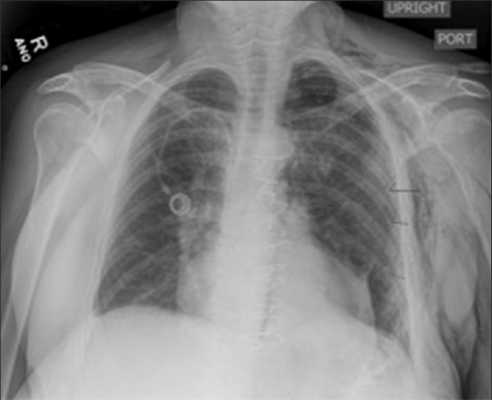

Ипсилатеральный пневмоторакс

Контралатеральный пневмоторакс